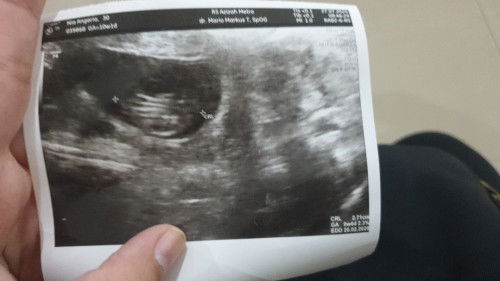

sharing yah bun hppt 17 mei telat 1 hari tespek positif langsung ke dokter kandungan hasilnya msih penebalan rahim lanjut 2 minggu kemudian kontrol udh ada kantung sempat kepikiran apa hamil ksoong untuk mengatasi kecemasan tepat hari ini kontrol hasil usg 7minggu hamil ga ngerasa apa² sehat2 yah buat kita semua bunda diberi kelancaran dan yg msih jdi pejuang garis 2 tetap semangat waktu Tuhan pasti yang tepat dan terbaik😇😇😇 ##Sharing_dong_Bund